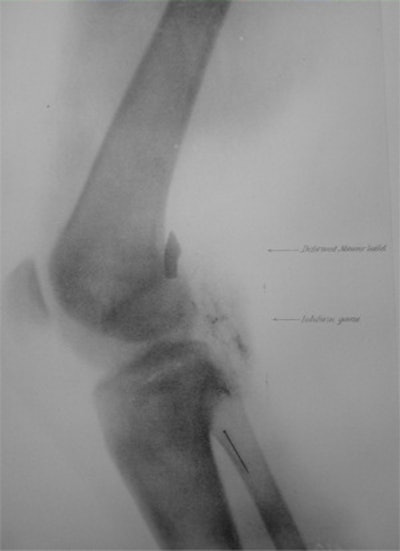

The illustration shows a radiograph of a bullet in the elbow of a native soldier taken by Maj. Beevor.The River War

Private John Gretzer (left) received a bullet in his brain, which an x-ray detailed. Illustrated is a Mauser bullet in in the brain of John Gretzer (center) and the knee of Samuel Davis (right).